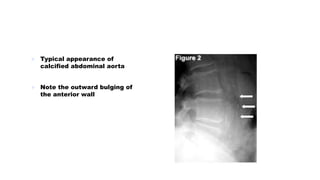

Vascular Calcification

๏ต Calcification of arteries seen

on x-rays is a sign of more

generalised atherosclerosis.

๏ต Occasionally vascular

calcification seen on an

abdominal X-ray reveals an

unexpected aneurysm

๏ต Typical appearance of

calcified abdominal aorta

๏ต Note the outward bulging of

the anterior wall

Vascular Calcification ๏ต Calcificationof arteries seen on x-rays is a sign of more generalised atherosclerosis. ๏ต Occasionally vascular calcification seen on an abdominal X-ray reveals an unexpected aneurysm

๏ต Typical appearanceof calcified abdominal aorta ๏ต Note the outward bulging of the anterior wall